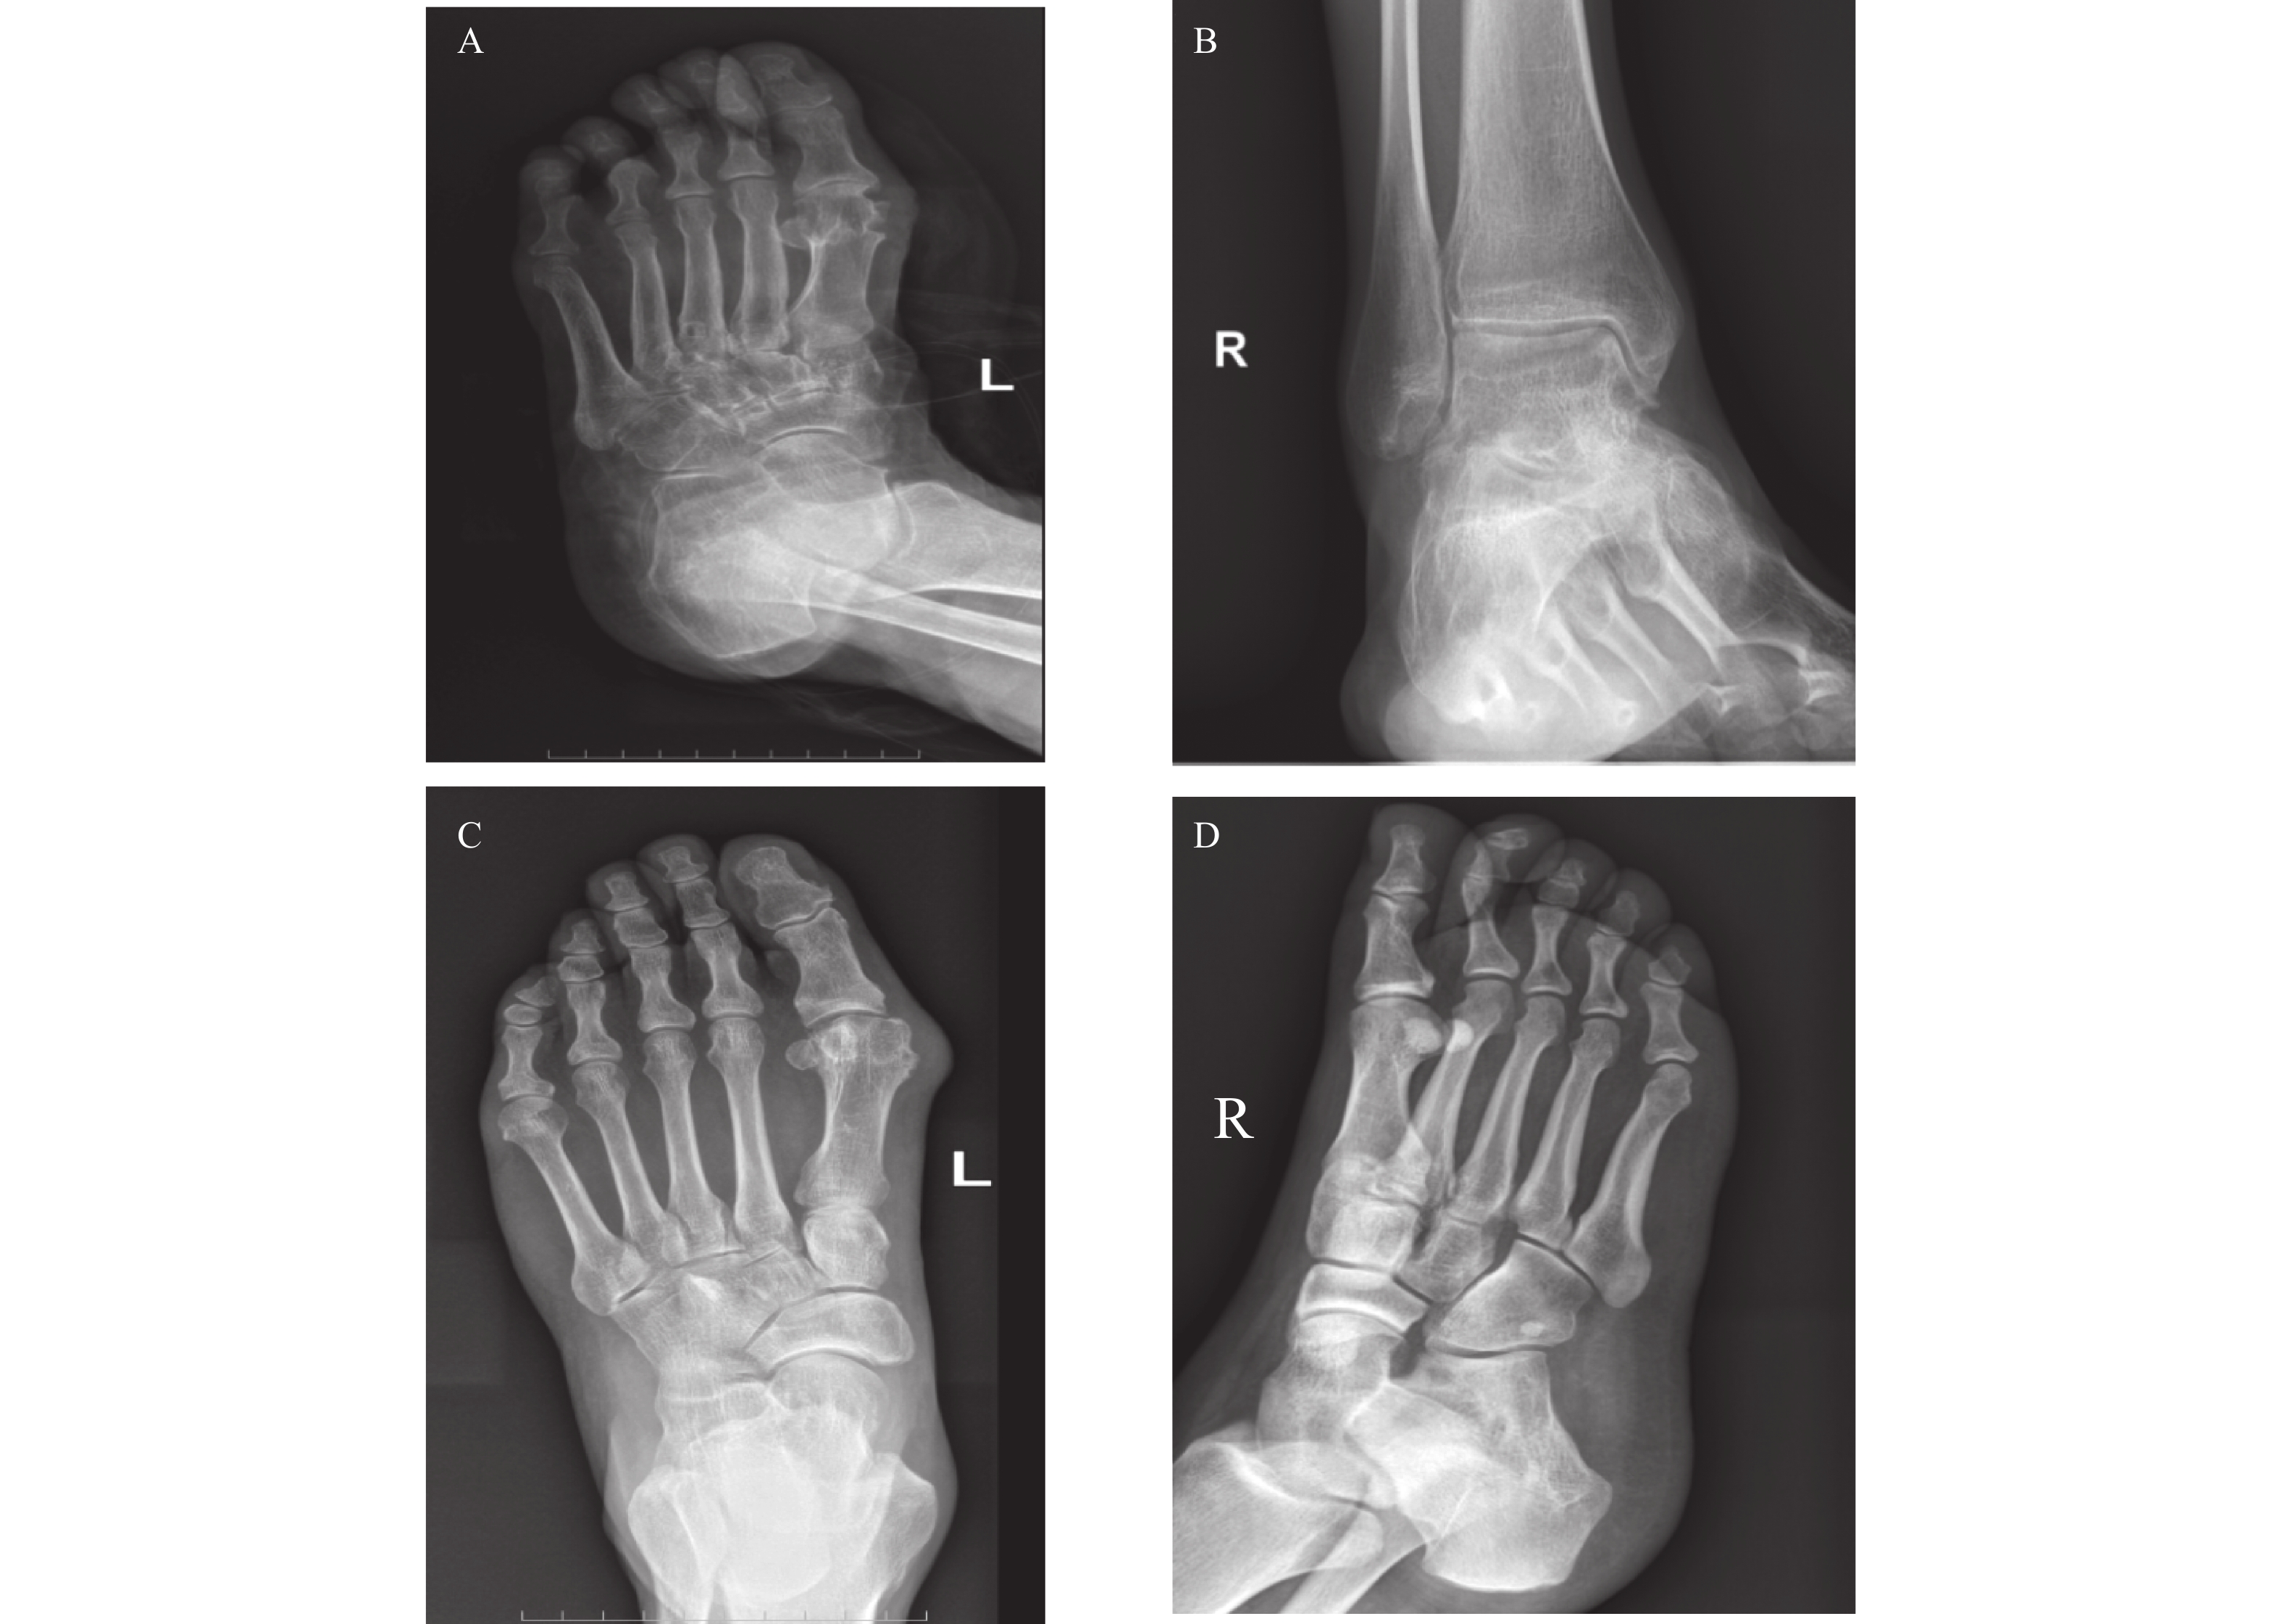

Clinical and Pathological Characteristics of Non-small Cell Lung Cancer with Pleural Effusion at Different Hematocrit Levels and Their Correlation with Prognosis

Ruwei JIANG, Lijun XU, Huiru WANG, Siyu HUANG

2026, 47(4): 155-164. doi: 10.12259/j.issn.2095-610X.S20260419

Abstract:

Objective   To investigate the clinical influencing factors of hematocrit (HCT) levels in non-small cell lung cancer (NSCLC) patients with pleural effusion (PE), and to analyze the impact of HCT levels on the prognosis of patients.   Methods  A total of 125 patients with NSCLC complicated with PE admitted to the People’ s Hospital of Yingshang County, Anhui Province from January 2020 to May 2025 were selected. The patients were divided into high HCT group (>39.84%), intermediate HCT group (36.52%–39.84%), and low HCT group (<36.52%) according to the tertiles of HCT levels after 4 cycles of treatment (subsequent analyses were all based on this time point). Stepwise regression analysis was used to correct the relationship between clinicopathological characteristics and HCT levels. Multivariate logistic regression was used to analyze the independent correlation between HCT levels and poor prognosis, and further subgroup analyses were conducted by stratifying blood routine indicators, carcinoembryonic antigen (CEA), and Ki67 nuclear-associated antigen (Ki67). Sensitivity analysis was conducted using the E-value method. Interval likelihood ratio, receiver operating characteristic (ROC) curve and area under the curve (AUC), and restricted cubic spline (RCS) were used to analyze the prediction of HCT levels on poor prognosis and the dose-response relationship between them. Kaplan-Meier survival curves were used for survival analysis.  Results  There were statistically significant differences in gender, age, lymph node metastasis, degree of differentiation, tumor stage, smoking history, HCT, lymphocyte (LY) count, neutrophil (NE) count, neutrophil-lymphocyte count ratio (NLR), eosinophil (EOS) count, CEA, Ki67, hemoglobin (Hb), ferritin (Fer), transferrin saturation (TSAT), albumin (ALB), C-reactive protein (CRP) levels , objective response rate and disease control rate among the three groups of patients (all P < 0.05). Gender, smoking history, tumor stage, and lymphatic metastasis were closely related to HCT levels (P < 0.05). HCT levels at each time point after treatment were significantly higher in the good prognosis group compared to the poor prognosis group (P < 0.05). After adjusting for confounding factors, there was still an independent correlation between HCT levels and the risk of poor prognosis (OR = 1.472, 95%CI: 1.345~1.620). HCT levels were associated with the prognosis of patients with NSCLC complicated with PE within different ranges of NE, LY, NLR, EOS, CEA, and Ki67. The E-value in the sensitivity analysis was 3.983. Low HCT levels could significantly increase the risk of poor prognosis, with a positive likelihood ratio of 6.468 (95%CI: 2.703~15.478)(P < 0.001), high HCT levels could significantly reduce the risk of poor prognosis, with a likelihood ratio of 0.064 (95%CI: 0.009~0.450)(P < 0.05). HCT levels had high predictive efficacy for poor prognosis in the overall population and different gender groups, with AUC of 0.940 (95%CI: 0.733~0.988), 0.823 (95%CI: 0.767~0.876), and 0.844 (95%CI: 0.753~0.903) respectively, and the optimal cut-off values for HCT levels were 36.24%, 32.89%, and 35.35% respectively. There was a non-linear dose-response relationship between HCT levels and the risk of poor prognosis in the overall population and different gender groups (Pfor non-linear < 0.05) . The progression-free survival (PFS) of patients with medium and high HCT levels was significantly higher than that of patients with low HCT levels (P < 0.05) .  Conclusion   Low HCT levels significantly increase the risk of poor prognosis in NSCLC patients with PE. When HCT≤36.24%, the association strength between HCT levels and poor prognosis risk is markedly increased, and this association exists at different levels of NE, LY, NLR, EOS, CEA, and Ki67. Comprehensive monitoring of these indices in clinical diagnosis and treatment has important clinical value for assessing prognosis in these patients.